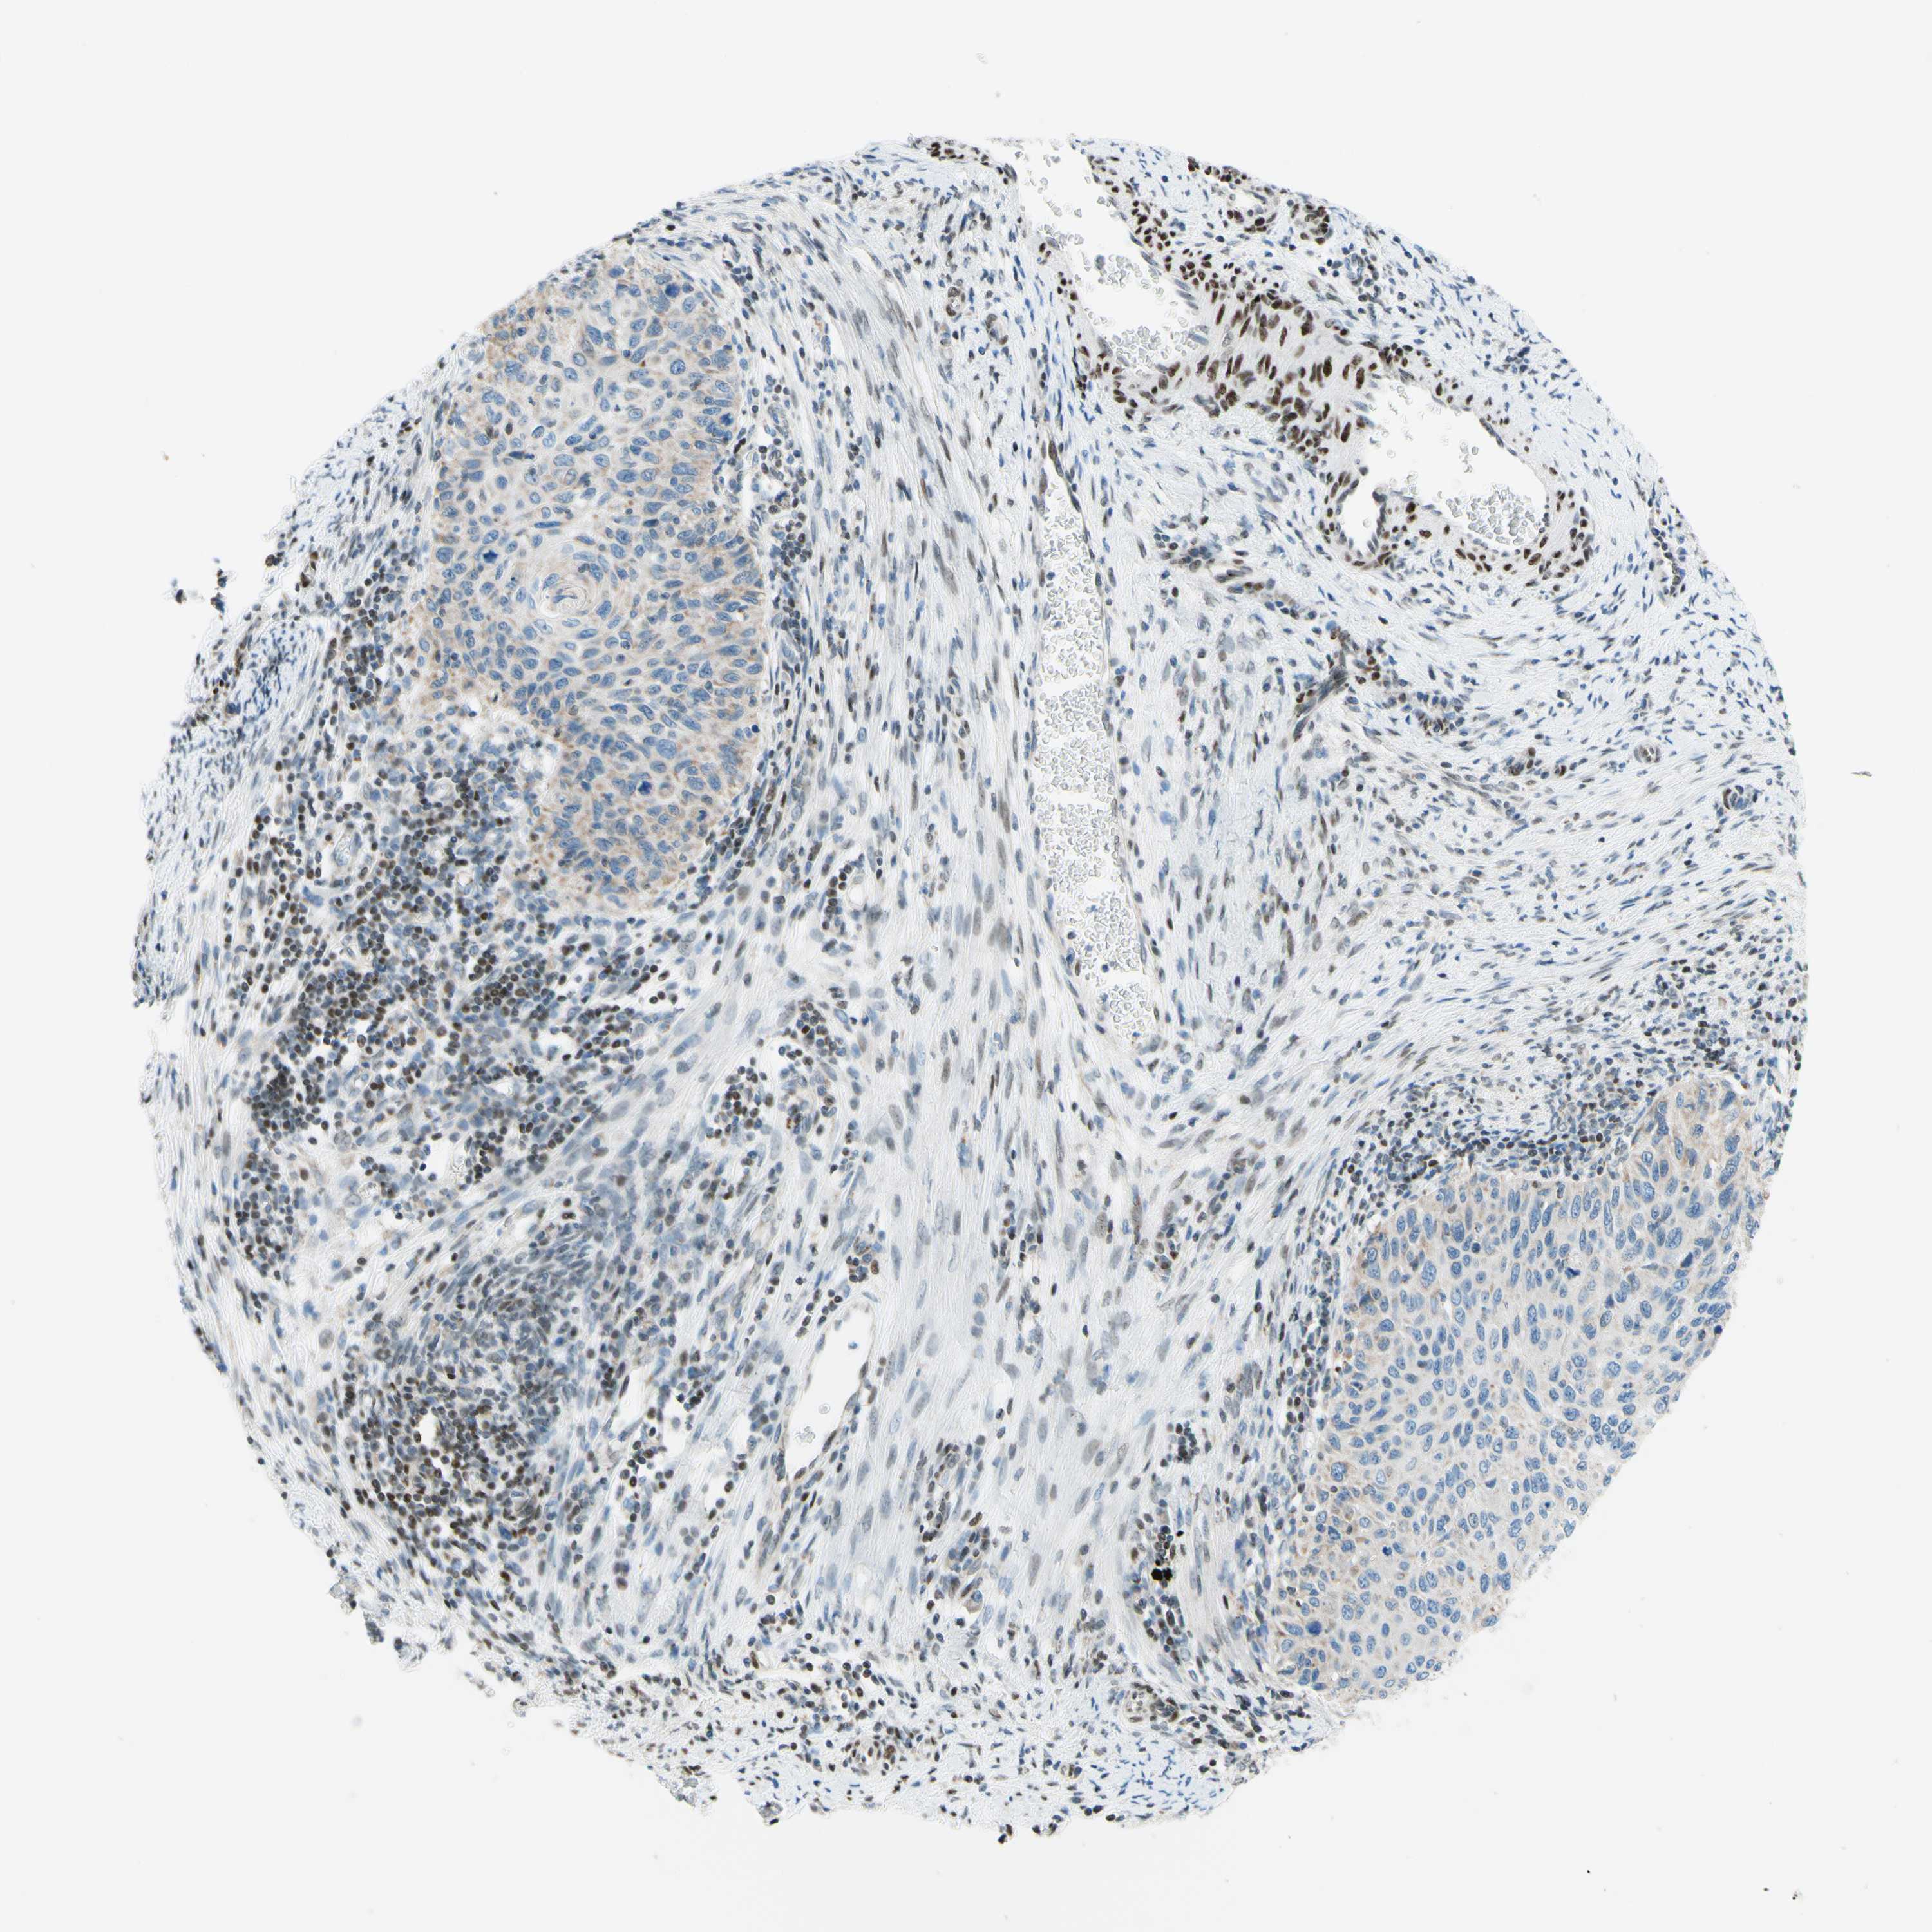

CERVICAL CANCER - Protein expressioni

A mouse-over function shows sample information and annotation data. Click on an image to view it in a full screen mode. Samples can be filtered based on level of antibody staining by selecting one or several of the following categories: high, medium, low and not detected. The assay and annotation is described here.

Note that samples used for immunohistochemistry by the Human Protein Atlas do not correspond to samples in the TCGA dataset.

Antibody stainingi

Antibody staining in the annotated cell types in the current human tissue is reported as not detected, low, medium, or high, based on conventional immunohistochemistry profiling in selected tissues. This score is based on the combination of the staining intensity and fraction of stained cells.

Each image is clickable and will lead to virtual microscopy that enables deeper exploration of all samples and also displays staining intensity scores, fraction scores and subcellular localization as well as patient and tissue information for each sample.

Antibody HPA048677

Antibody HPA056480

Antibody CAB011574

Staining

High

Medium

Low

Not detected

Intensity

Strong

Moderate

Weak

Negative

Quantity

>75%

75%-25%

<25%

None

Location

Nuclear

Cytoplasmic/membranous

Cytoplasmic/membranous,nuclear

Squamous cell carcinoma, NOS